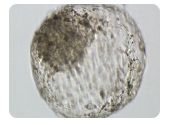

随着辅助生殖技术的不断进步,三代试管婴儿技术(PGD/PGS)在浙江地区逐渐普及,为遗传病筛查和提高成功率提供了有力保障。本文将为您详解浙江地区三代试管婴儿的流

试管婴儿技术的诞生,是医学界的一次重大突破,它让那些因身体原因无法自然受孕的夫妇看到了生育的希望。在我国浙江,试管婴儿技术的发展也为无数家庭带来了新的希望。那么

试管婴儿技术(IVF)作为解决不孕不育难题的重要手段,已经帮助无数家庭迎来了新生命。天津,作为中国北方的医疗重镇,拥有先进的医疗设施和专业的医疗团队。本文将为您